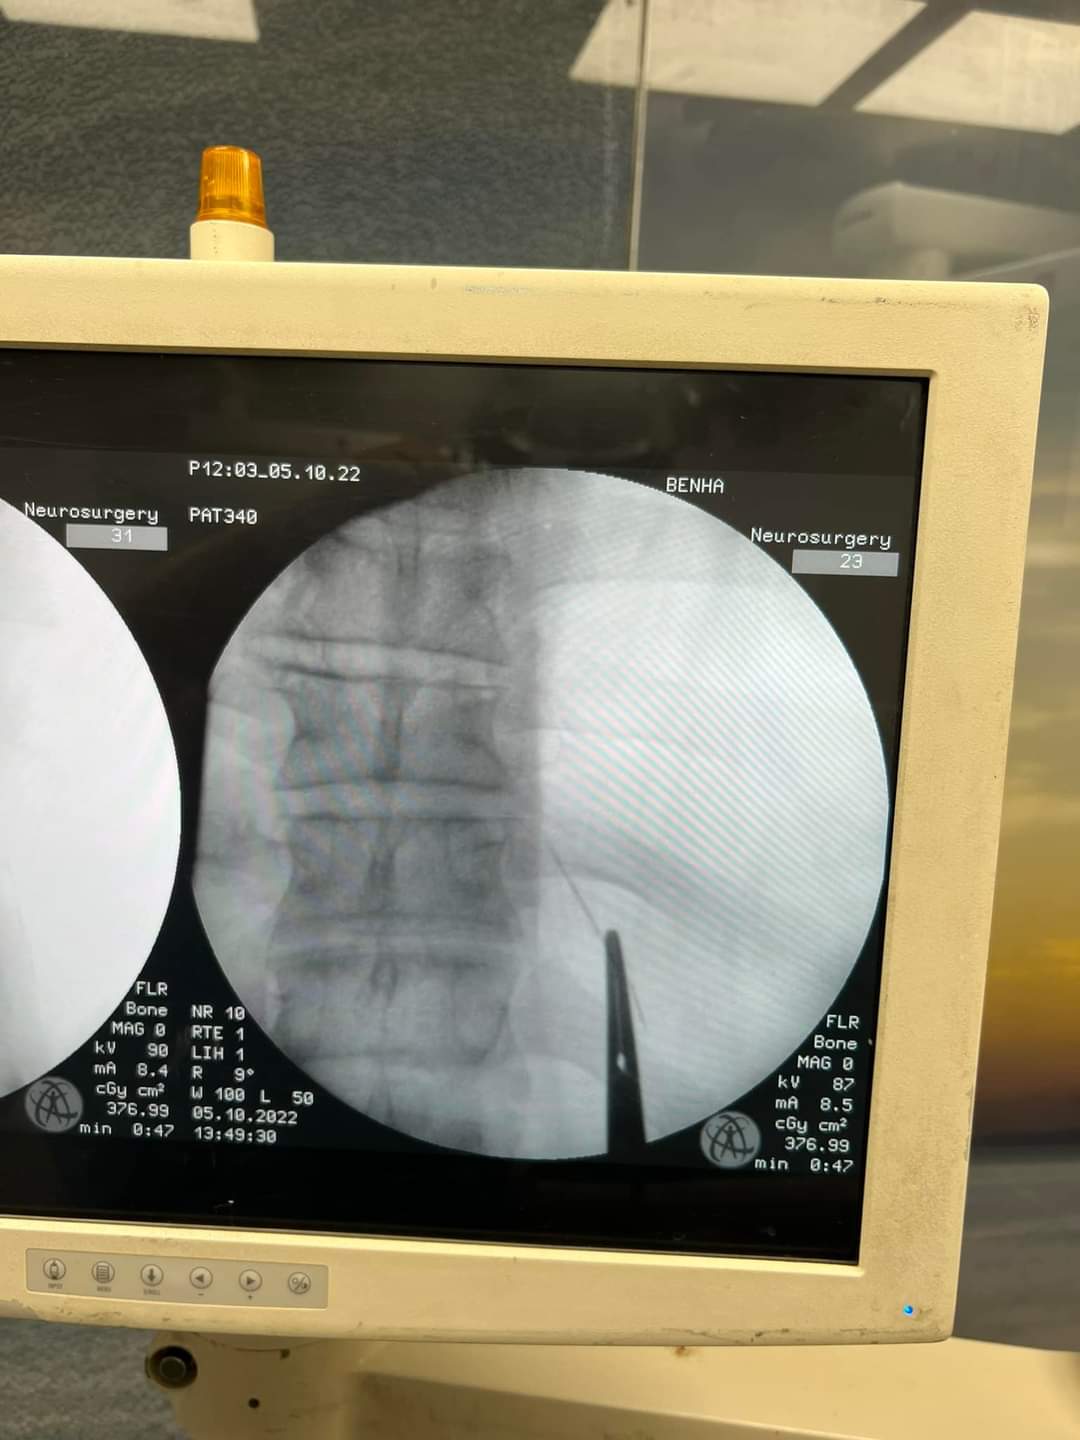

وأوضح البيان أنه تم حجز المريض بالقسم وتجهيزه لعملية سريعة، تم فيها الاستعانة بجهاز الأشعة الملحق بغرف العمليات (C-arm)، حيث تم تحديد مكان الإبرة والفتح الجراحي عليها مباشرة، واستخراجها بنجاح، ولكن على هيئة قطع منكسرة بسبب الصدأ، نظرا لبقائها طوال هذه المدة.